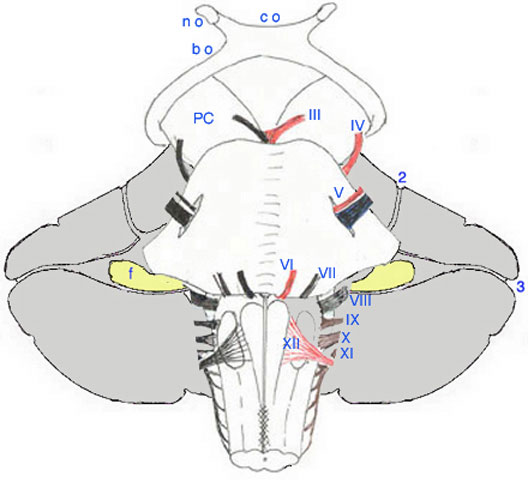

Systmatisation

est reprsent en coupe frontale, schmatis lÕextrme, y figurent les

repres utiles au trac des diffrentes voies.

Sch.20 – Canevas du nvraxe |

Dchiffrer les lgendes partir du

haut : - Les chiffres : numrotation des aires corticales fronto-parito- temporales.. - T : Thalamus - PC : Pdoncule Crbral - nr : noyau rouge - s, m, i : pdoncules crbelleux

sup., moyen & infer. - v4 : Losange dlimitant le 4”

ventricule - np : noyaux pontiques - nf : noyau fastigial |

- ni : noyaux interposs - nd : noyau dentel - nv : noyaux vestibulaires - nvl : noyau vestibulaire latral - :ZL : Zone latrale - Zi : Zone intermdiaire - Zm ; Zone mdiale - Zfn : Zone floculo-nodulaire - ob : olive bulbaire - nC : noyau de Clarke - fscd : faisceau spino-crbelleux

dorsal - fscv : faisceau spino-crbelleux

ventral |